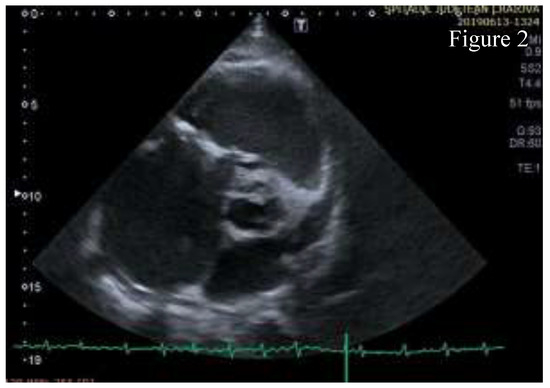

Figure 2.

Parasternal short axis view- the anterior cusp of the tricuspid valve is thickened and calcified, chordae tendinae are thickened, right atrium is dilated and a calcification area is found on the aortic right coronary cusp.